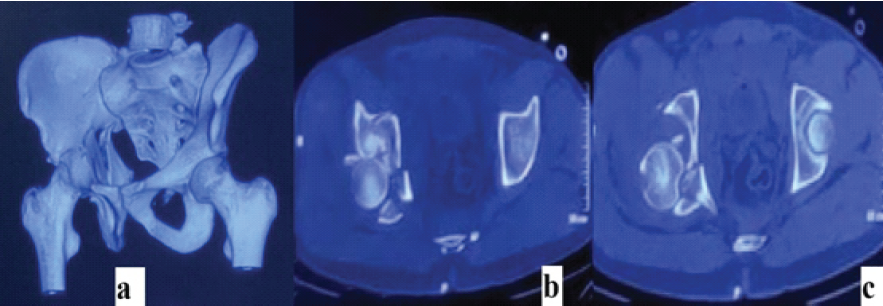

A 26-year-old male presented after a high-velocity road traffic accident with isolated left hip trauma. He was hemodynamically stable with no associated head, thoracoabdominal, or spinal injuries. The left lower limb appeared shortened and internally rotated, with severe hip pain and restricted active and passive motion. Distal pulses were palpable, and sensory and motor examination of the sciatic and femoral nerve distributions was normal. Anteroposterior pelvic radiographs (Fig. 1) and Judet views showed disruption of both the iliopectineal and ilioischial lines, indicating involvement of the anterior and posterior columns, with preservation of the obturator foramen, consistent with a both-column pattern. Computed tomography (CT) with three-dimensional reconstruction confirmed an anterior column posterior hemi-transverse acetabular fracture involving the weight-bearing dome and posterior wall (Fig. 2) according to the Letournel classification.

Figure 2: Computed tomography of the pelvis at presentation – (a) three-dimensional reconstruction demonstrating a complex acetabular fracture involving both anterior and posterior columns; (b and c) axial computed tomography sections confirming fracture extension through the weight-bearing dome with involvement of the posterior wall.